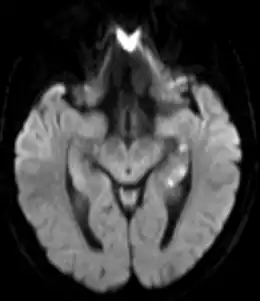

Description de l'image Transiente globale Amnesie MRT DWI axial.png.

L'examen neurologique est normal pendant et après la crise ainsi que l'imagerie cérébrale[7]. Il peut exister cependant des images punctiformes au niveau de l'hippocampe à l'IRM cérébrale, mais qui sont retardées et transitoires[10], ce qui explique que l'on passe souvent à côté. Le déficit dure, en moyenne, six heures[7].